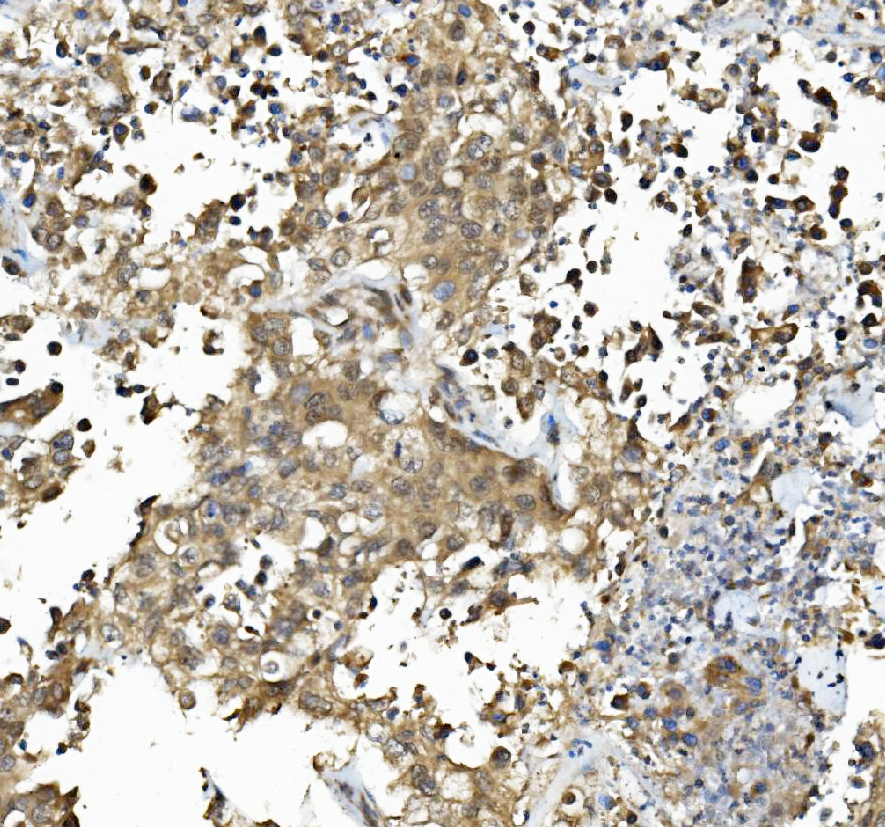

IHC analysis of Caspase 6/CASP6 (large) using anti-Caspase 6/CASP6 (large) antibody (BA3969).

Caspase 6/CASP6 (large) was detected in a paraffin-embedded section of human pancreatic cancer tissue. Biotinylated goat anti-rabbit IgG was used as secondary antibody. The tissue section was incubated with rabbit anti-Caspase 6/CASP6 (large) Antibody (BA3969) at a dilution of 1:200 and developed using Strepavidin-Biotin-Complex (SABC) (Catalog # SA1022) with DAB (Catalog # AR1027) as the chromogen.